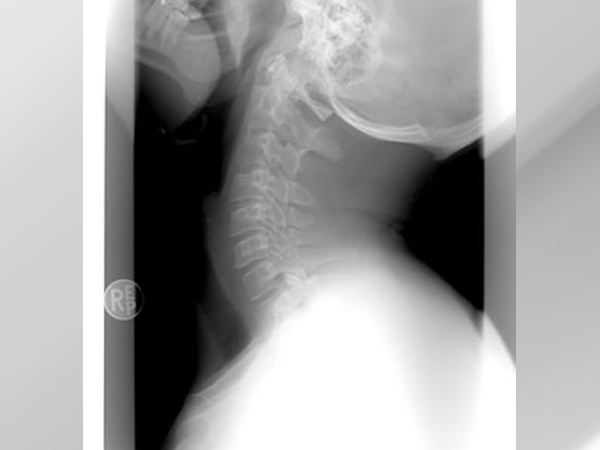

Diagnosis Of Spinal Stenosis

Your doctor may first ask you about the signs and symptoms, followed by a general idea about your medical history. You would be examined physically depending on which the following imaging tests might be recommended:

- X-rays: An X-ray of your spine can reveal bony changes that might be the reason behind narrowing the space within the spinal canal.